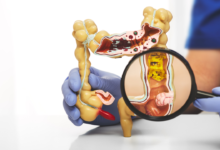

Constipation is a common digestive issue characterized by infrequent, difficult, or painful bowel movements. It occurs when the stool becomes hard and dry, making it harder to pass. Typically, a person is considered constipated if they have fewer than three bowel movements per week. Other symptoms may include a bloated feeling, abdominal discomfort, and straining during bowel movements.